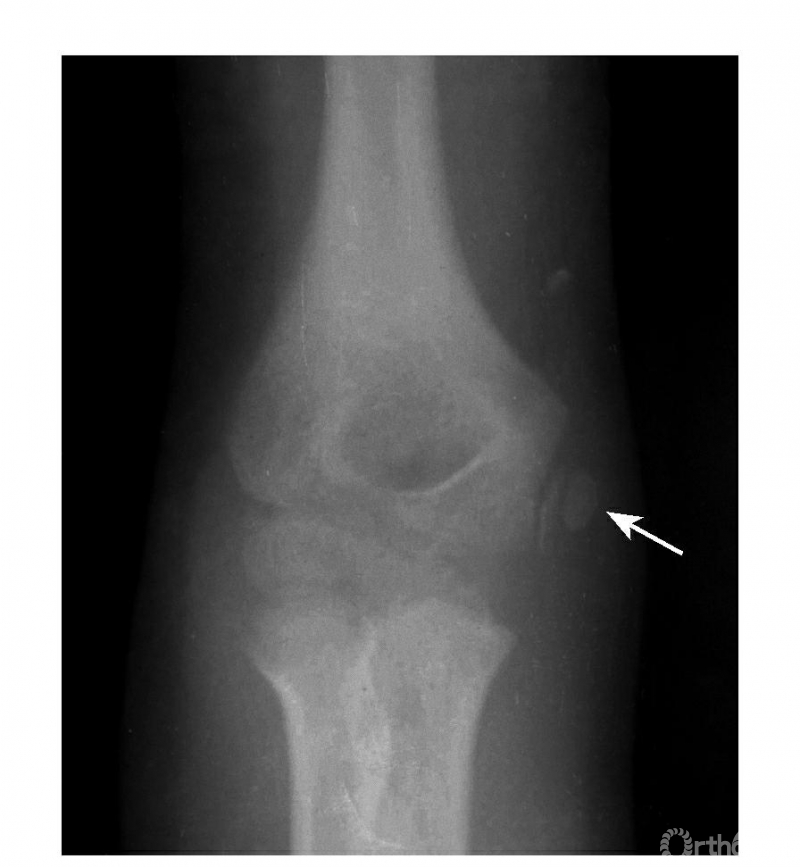

例2:内上髁骨骺并带内髁骨块向外翻转移位,达关节水平(图5)。

图5

Ⅲ度损伤:

例1:内上髁骨骺撕脱并移至尺肱关节间(图6)。

图6

例2:内上髁撕脱骨折,骨块移至尺肱关节间(成人)(图7)。

图7